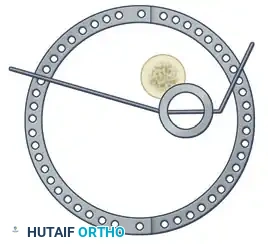

Step 3: Multi-Planar Fracture Reduction Using Olive Wires

Olive wires (wires with a small metal bead or "olive" forged into them) are powerful tools for translating bone fragments and achieving final reduction.

- Coronal Plane Correction: Use arched olive wires for final fracture reduction. For residual displacement in the coronal plane, place an olive wire in a transverse fashion (ensuring it passes through a safe anatomical zone).

- Apply tension to the wire without securing it tightly to the frame on the opposite side. The tensioner will pull the olive—and consequently the bone fragment—toward the tensioner, correcting the translation.

- Use continuous image intensification to ensure adequate reduction is achieved without over-translating the fragment.

- Once adequate correction is obtained in the coronal plane, secure the wire to the frame on the olive side.

- Sagittal Plane Correction: If further correction is required in the sagittal plane, connect another olive wire in an arched fashion. Tensioning this arched wire will impart a directional force vector to the bone, achieving final sagittal alignment.